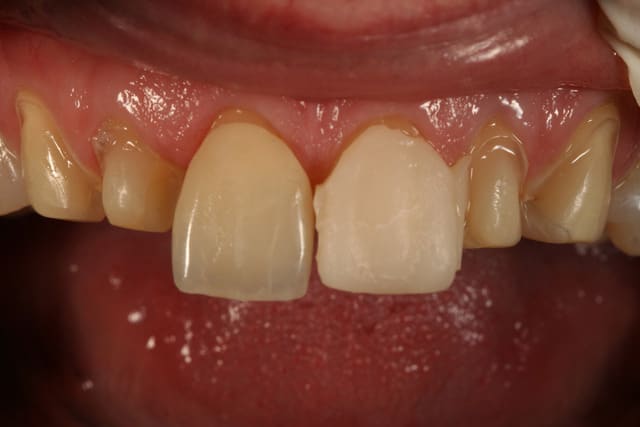

essayage, et comme on peut le voir sur la première photo, c'est bizarement long par rapport au provisoire ...

pourtant le prothésiste avait un alginate des mocks-up

j'ai mis du sealtemp et essayé tout ça, c'est trop long

par contre, je me dis que je suis resté trop supra-gingival sur mes préparations, ça se voit trop, même si la patiente découvre peu, elle découvre un peu et j'aurais du aller plus juxta.

voilà le resultat collé

je suis resté trop supragingival, mais la patiente est très contente (ouf, c'est l'essentiel !)